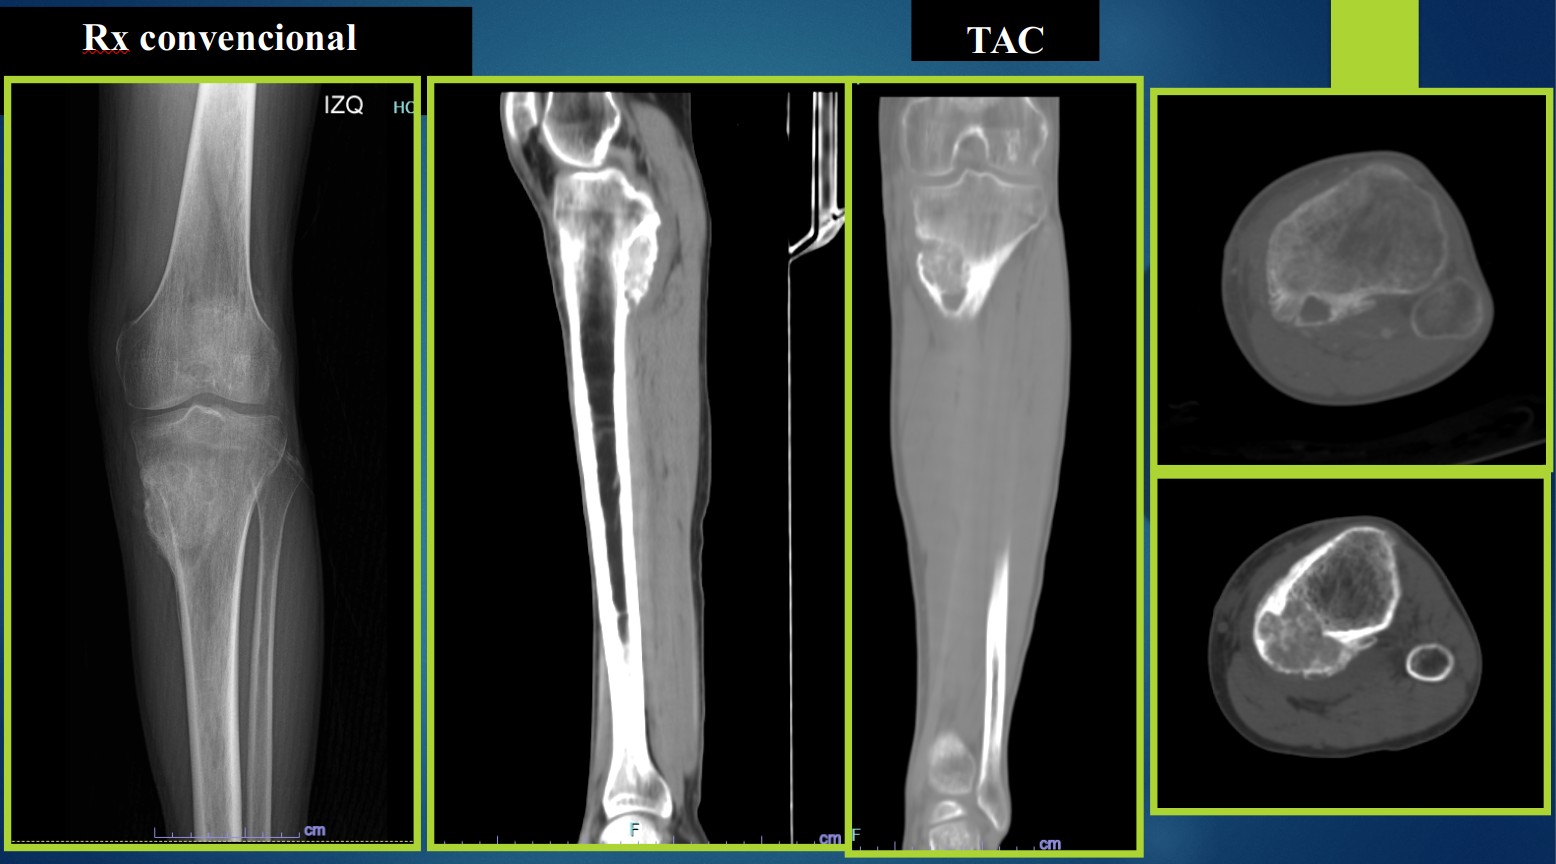

Dolor en rodilla izquierda secundaria a traumatismo no especificado

1. ¿Cuál es su posibilidad diagnóstica con los estudios de imagen?

El Osteoblastoma es una neoplasia benigna localmente agresiva formadora de hueso trabecular revestido por osteoblastos que mide más de 2 centímetros. (1) Se describió primero por Jaffe y Lichtenstein en 1956 en dos publicaciones diferentes. Representa menos del 1% de los tumores primarios de hueso. Se origina en la medula de huesos largos y afecta el arco neural posterior con extensión al cuerpo vertebral. Es Frecuente en adolescentes y adultos jóvenes entre la segunda y cuarta década de la vida, el 75% de los pacientes tienen menos de 25 años al momento del diagnóstico, con predominio en el sexo masculino (2:1). (1,2). Clínicamente hay dolor, edema, disminución en los rangos de movimiento y cuando ocasionan efecto de masa se asocia a paresia, parestesias y paraplejia. Radiológicamente se caracteriza por ser una lesión blástica, expansiva, bien delimitada con halo radiolucente periférico, mineralización central. Histológicamente se identifican trabéculas óseas de forma irregular que se pueden interconectar con reborde de osteoblastos muchos de ellos con características epitelioides, escasos osteoclastos, estroma vascular y escasas mitósis no atípicas. (5). Por inmunohistoquímica son positivos a FOS en 60-83%de los casos. El principal diagnóstico diferencial es con el Osteosarcoma, el osteoma osteoide y el quiste óseo aneurismático, El tratamiento de elección es resección en bloque o resección intracompartamental. El osteoblastoma es de excelente pronóstico, el 20% presenta recurrencia local y es muy rara la transformación maligna. (1).